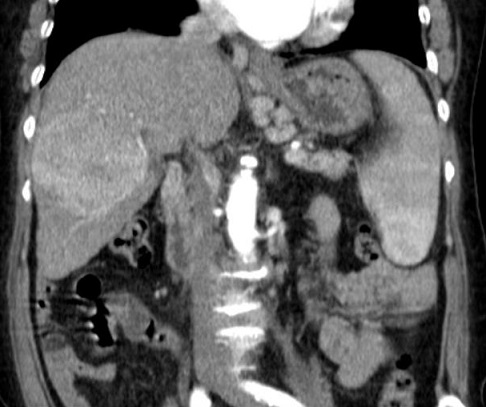

Mêm cas en coupe TDM

coronale temps arteriel: Image du tumeur en voyait

si net sur cette coupe . |